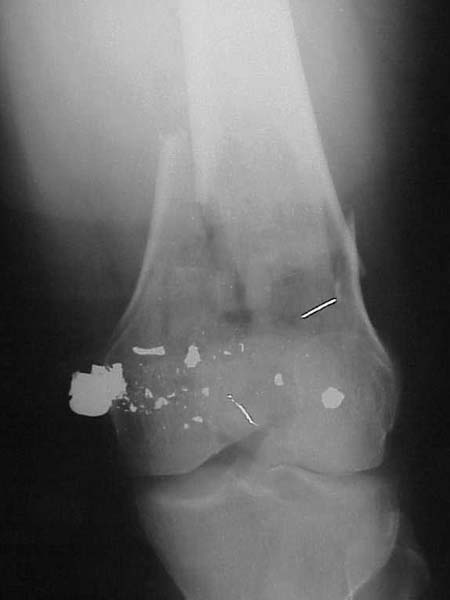

A male 31 y.o. addmitted to our unit today with the subject (see attachment). Injured in a car accident 1 month ago, since that he has been at bed traction. Other fractures are minor - undisplaced pubic rami and distal ulna.

What is your opinion about optimal program here? Is closed nailing a good option here? Articular part of condyles looks fine, but the lateral one seems to be too small and comminuted. Or external fixation as definitive method? Or open the fracture at least distally, fix condyles then nail?

Of course the only radiograms both the view of the femur (AP and LL) are not enough in order to assess the condyles. So I think a TAC of the knee could be useful.

A CT and knee xrays would help identify lateral condyle comminution and/or a "hoffa fragment" of the posterior condyle. I am concerned that the lateral cortex is not sufficient to give purchase for a retrograde IMN. blocking screws could improve this as a possibility.